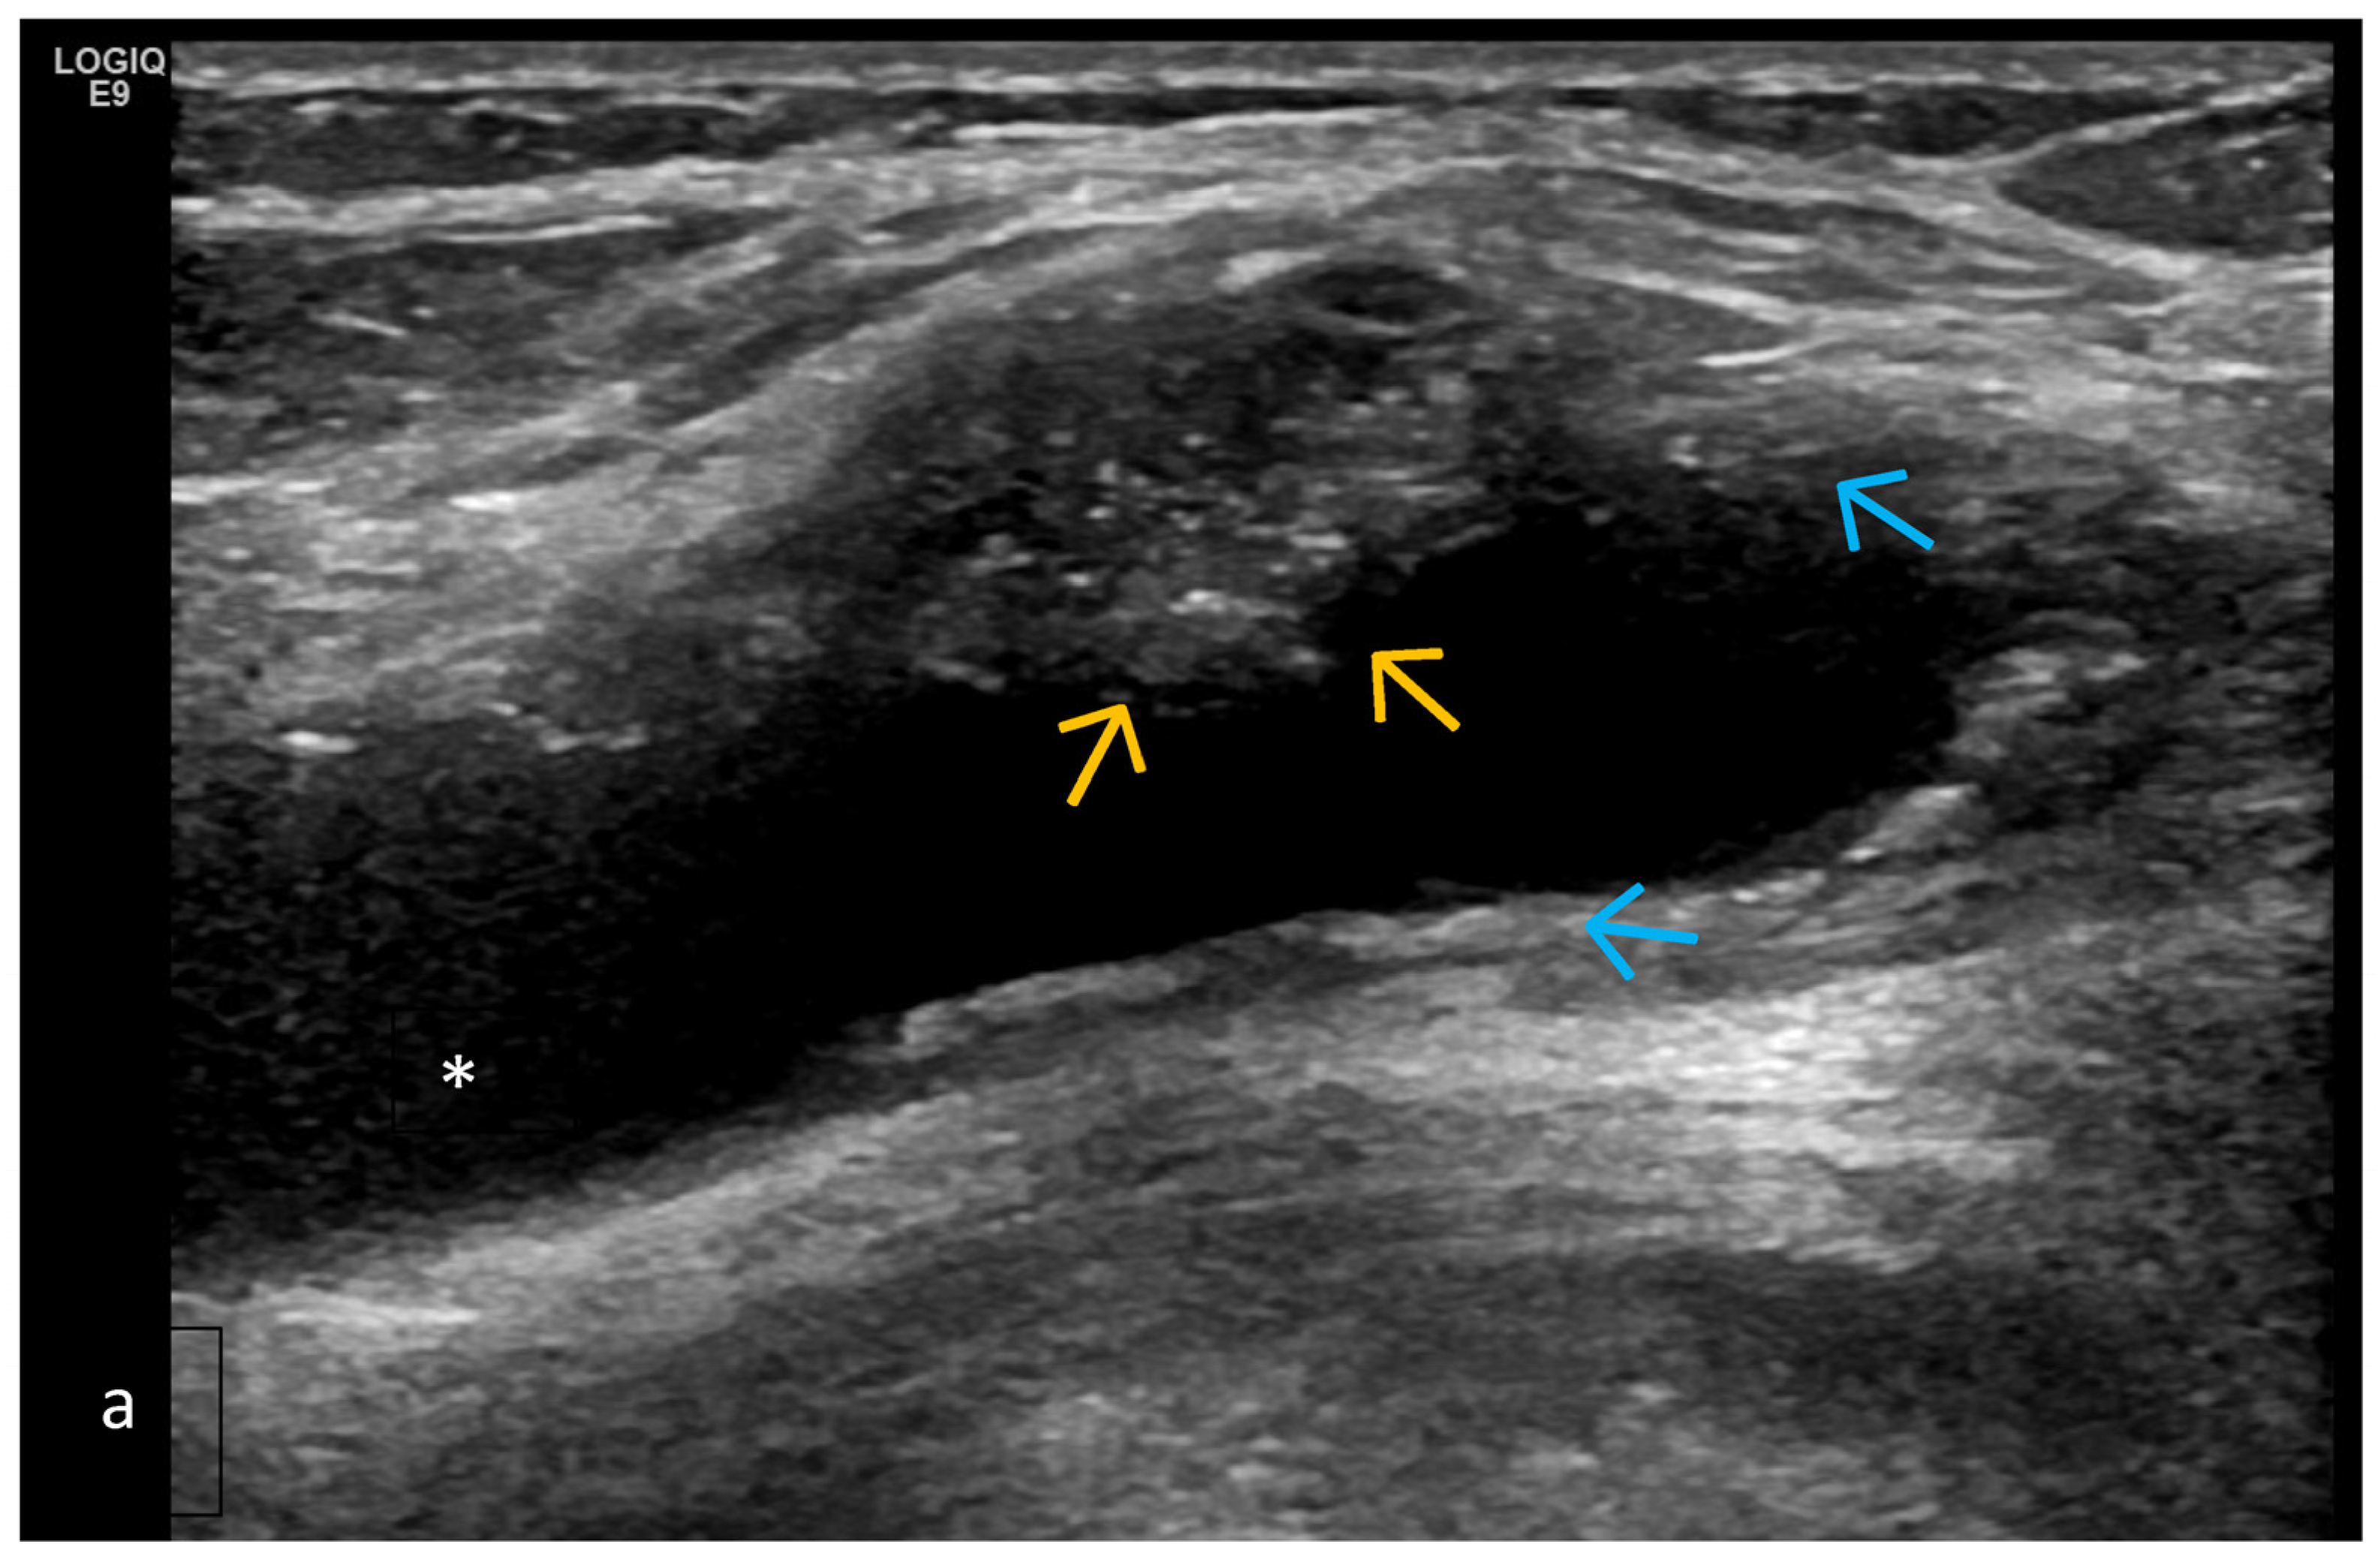

- Predominant intra-articular effusion (with minimal synovial proliferation (synovial sacs) and large intra-articular effusion;

- Predominant synovial proliferation, fat pads, and Hoffa synovitis (with a small amount of intra-articular effusion);